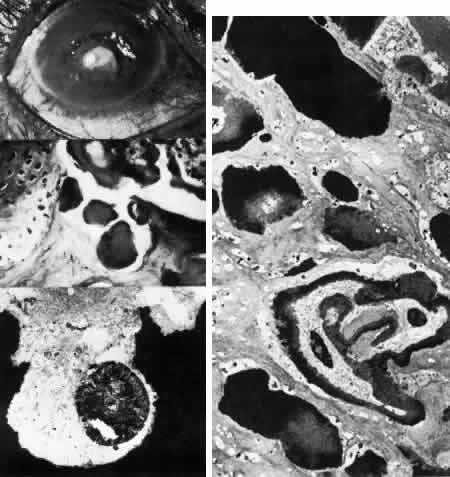

Fig. 11. Macular corneal dystrophy. Top left. Clinical appearance of cornea features diffuse haze extending to the limbus with superimposed, dense gray-white spots. Bottom left. Light photomicrograph of posterior cornea shows endothelial cells staining intensely positive for acid mucopolysaccharide. Guttate excrescences (*) of Descemet's membrane (DM) are frequent. The stroma also shows positive staining for acid mucopolysaccharide both diffusely extracellularly and intensely within keratocytes (circled) (colloidal iron × 500). Right. Transmission electron micrograph discloses typical fibrillary granular deposits within keratocytes (K), throughout the posterior layer of Descemet's membrane, and within the endothelial cells (En). The anterior banded region of Descemet's membrane (bracketed) is not affected (× 3500).

The lesions in macular corneal dystrophy stain intensely with alcian blue and colloidal iron, minimally with PAS, and not at all with Masson's trichrome. Birefringence is decreased. The lesions have been histochemically identified as an abnormal keratan sulfate-like glycosaminoglycan that accumulates extracellularly within the stroma and Descemet's membrane and intracellularly within keratocytes and endothelium.130

As would be typical of an autosomal recessively inherited condition, macular dystrophy presumably results from deficiency of a hydrolytic enzymes (sulfotransferase) and may thus be considered a localized mucopolysaccharidosis.131 The effect of altered glycosaminoglycan metabolism is evident at the cellular level; on transmission electron microscopy, keratocytes and endothelial cells exhibit distention of rough-surfaced endoplasmic reticulum cisternae. With the acridine orange technique, compensatory generalized hyperactivity of the lysosomal enzyme system has been demonstrated.132 Eventually the accumulated undigested storage products engorge the cells, and the cells ultimately degenerate or rupture. The derivation of these intracytoplasmic storage vacuoles from endoplasmic reticulum suggests that the biochemical lesion in macular dystrophy occurs at a different metabolic location than in the systemic mucopolysaccharidoses, since in the latter, storage products accumulate within lysosomelike intracytoplasmic vacuoles associated with the Golgi complex.133 Snip and associates134 were able to determine that the storage phenomenon affecting endothelium and Descemet's membrane is likely also primary, since the intracellular and extracellular lesions appear ultrastructurally comparable to those evident in the keratocytes and stroma.